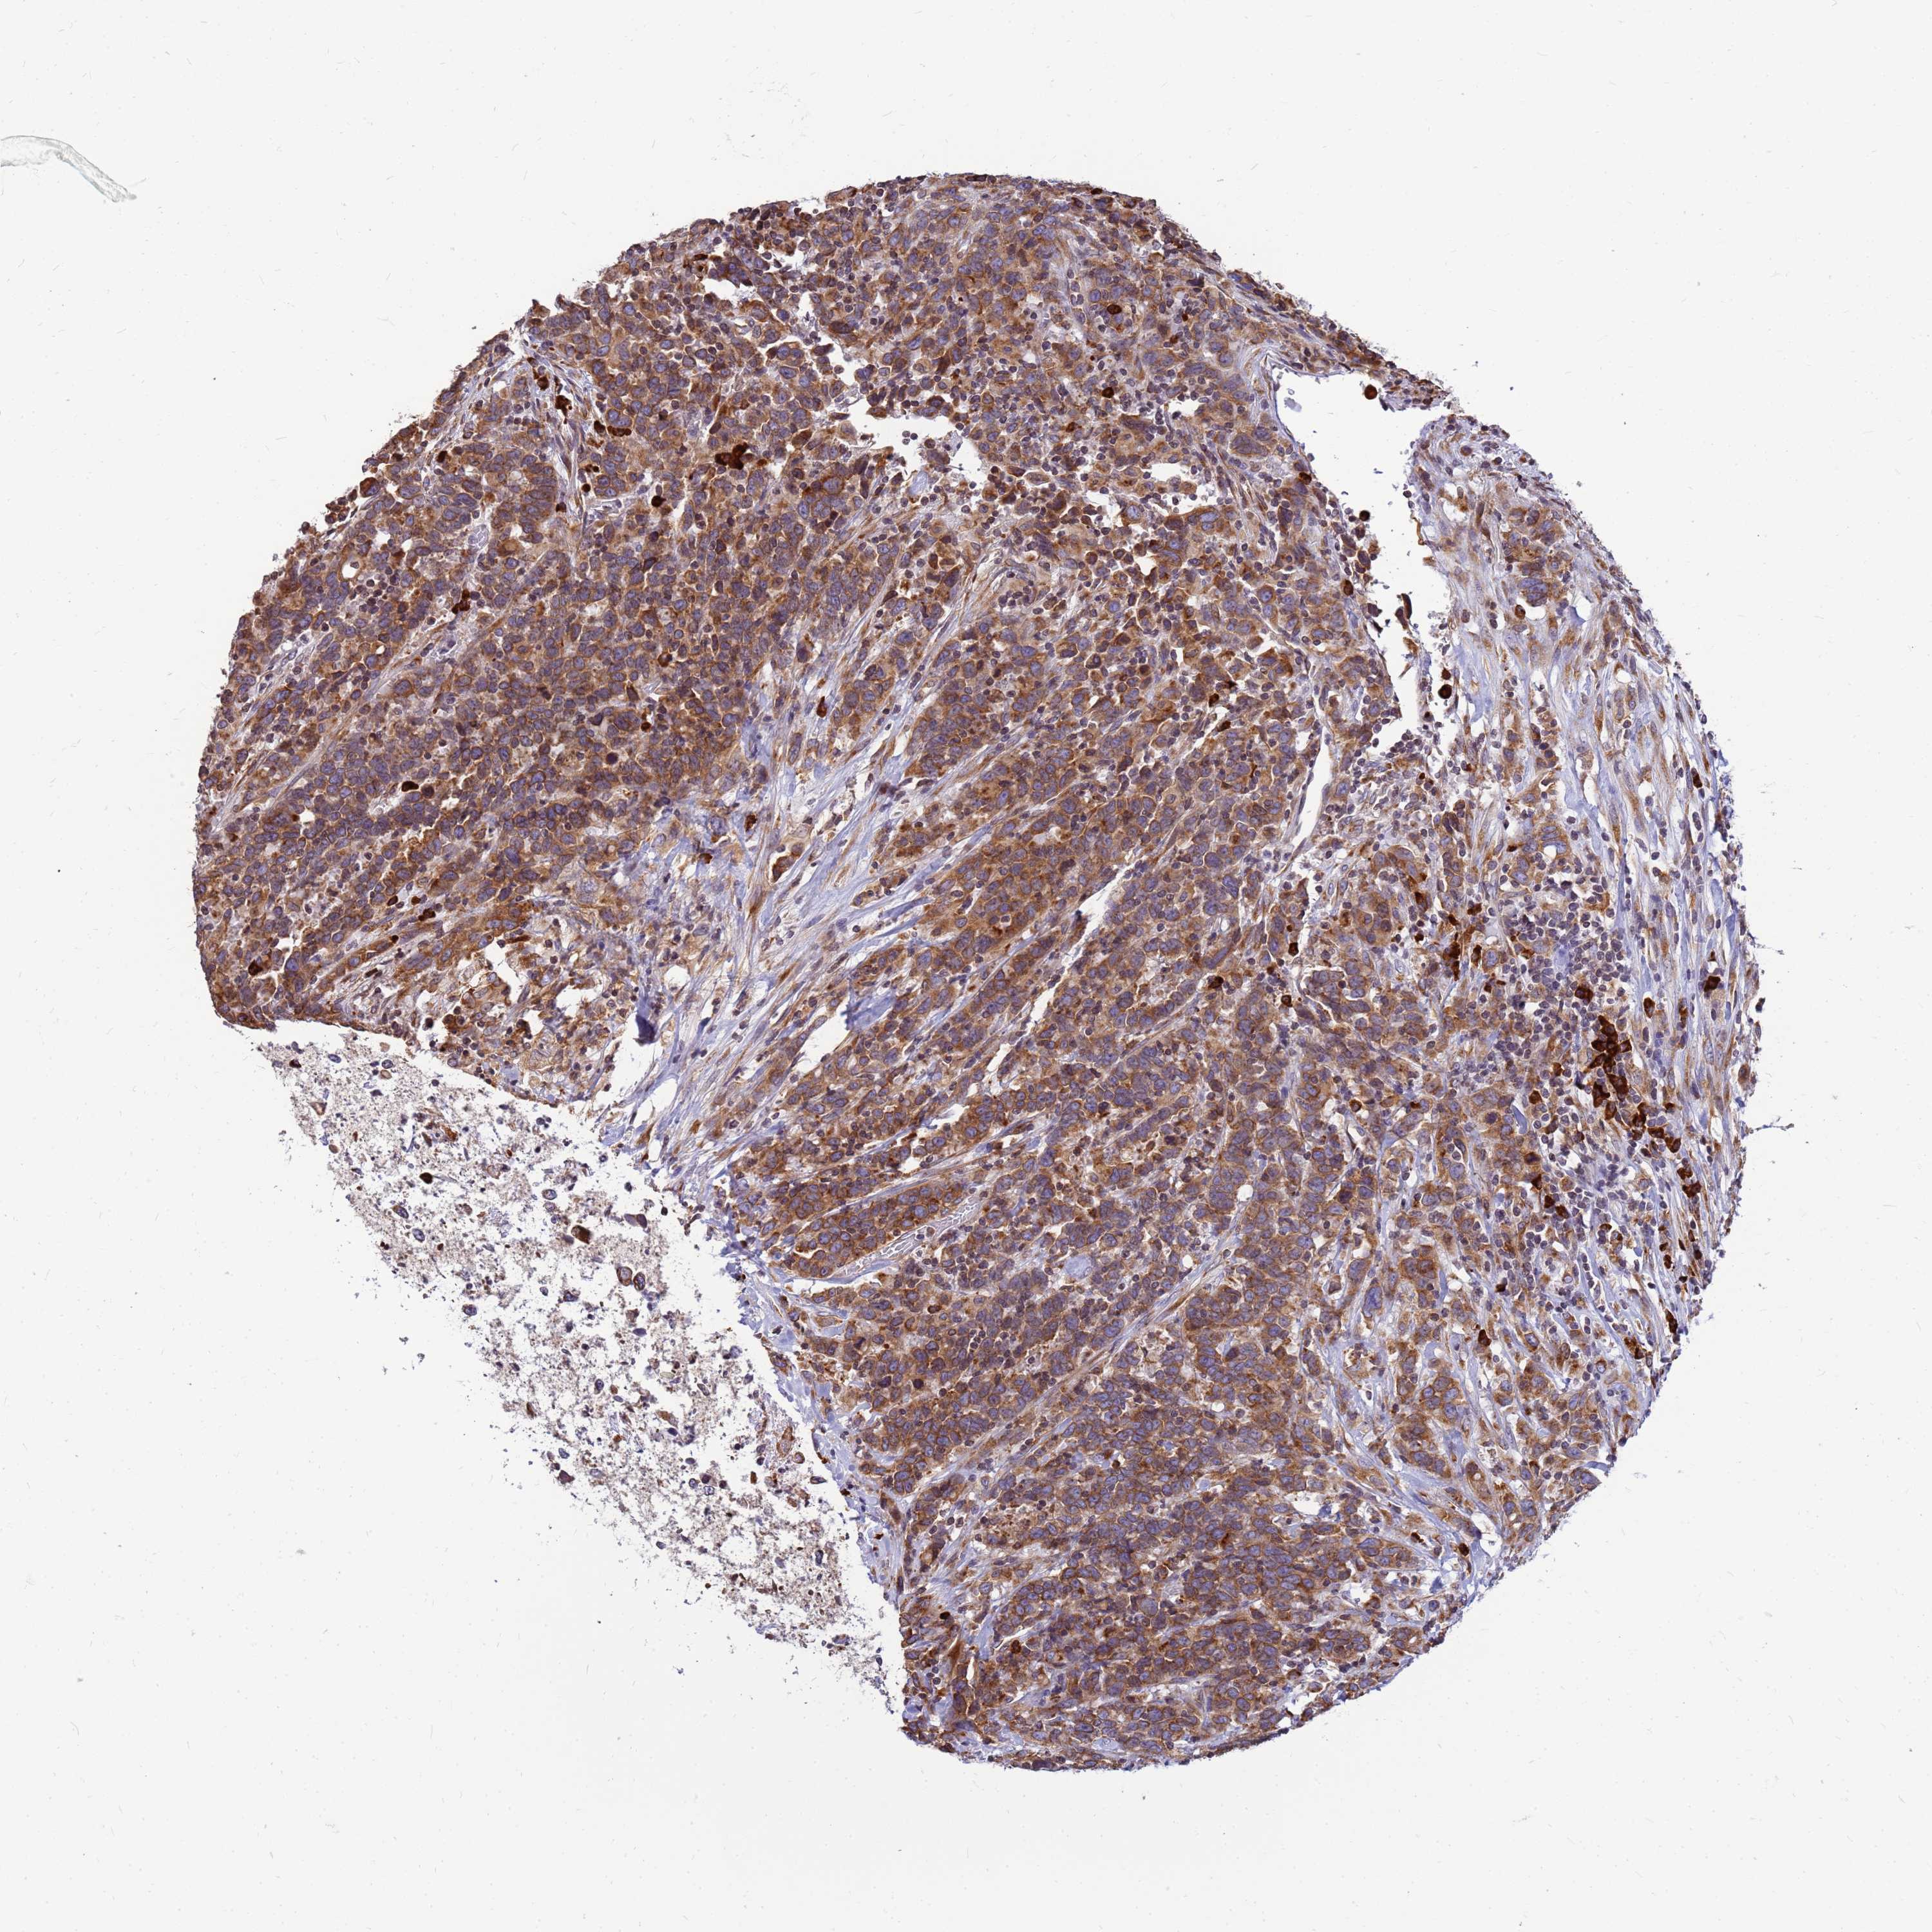

UROTHELIAL CANCER - Protein expressioni

A mouse-over function shows sample information and annotation data. Click on an image to view it in a full screen mode. Samples can be filtered based on level of antibody staining by selecting one or several of the following categories: high, medium, low and not detected. The assay and annotation is described here.

Note that samples used for immunohistochemistry by the Human Protein Atlas do not correspond to samples in the TCGA dataset.

Antibody stainingi

Antibody staining in the annotated cell types in the current human tissue is reported as not detected, low, medium, or high, based on conventional immunohistochemistry profiling in selected tissues. This score is based on the combination of the staining intensity and fraction of stained cells.

Each image is clickable and will lead to virtual microscopy that enables deeper exploration of all samples and also displays staining intensity scores, fraction scores and subcellular localization as well as patient and tissue information for each sample.

Antibody HPA045209

Staining

High

Medium

Low

Not detected

Intensity

Strong

Moderate

Weak

Negative

Quantity

>75%

75%-25%

<25%

None

Location

Nuclear

Cytoplasmic/membranous

Cytoplasmic/membranous,nuclear

Urothelial carcinoma, High grade